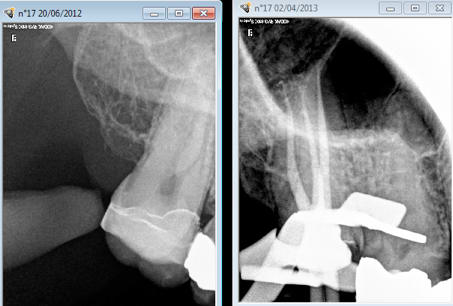

Tiens un onlay cerec qui s'est transformé en endo à la jean mich. Parce que ca mon pote tu vas en avoir. -)

Capture d e cran 2016 04 26 21.19 - Eugenol

Capture d  cran 2015 03 12 12.28 - Eugenol

chicot29

26/04/2016 à 23h27

Du coup jean mich a évité de passer par la case cerec pour traiter la 16. -)

Capture d e cran 2016 04 26 21.25 - Eugenol